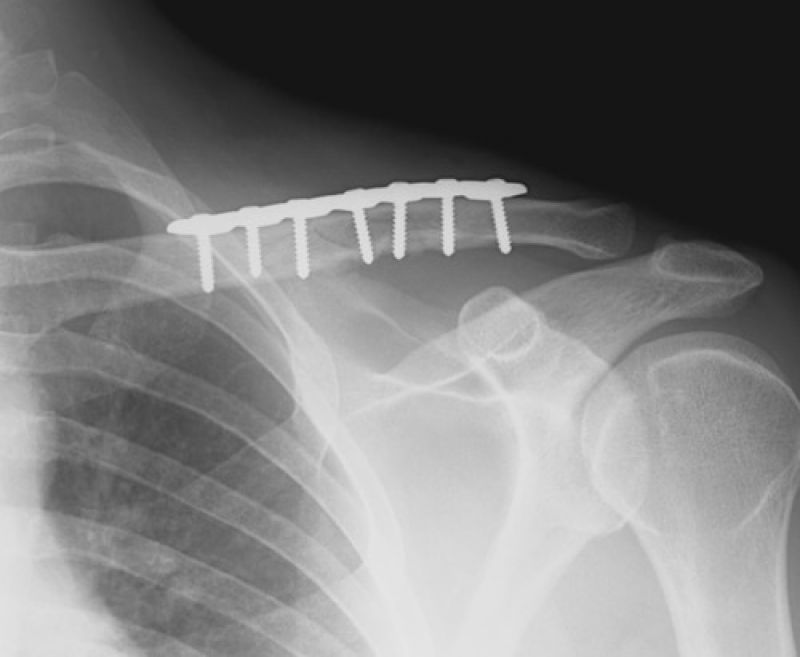

ਅੰਮ੍ਰਿਤਸਰ : ਹੱਡੀ ਟੁੱਟਣਾ ਜਾਂ ਫ੍ਰੈਕਚਰ ਹੋਣਾ ਕਈ ਪ੍ਰਕਾਰ ਕੇ ਹੋ ਸਕਦੇ ਹਨ। ਕਈ ਬਾਰ ਹੱਡੀ ਥੋੜੀ ਜਿਹੀ ਟੁੱਟਦੀ ਹੈ ਤੇ ਕਦੇ-ਕਦੇ ਉਸ ਵਿੱਚ ਵੱਡਾ ਫ੍ਰੈਕਚਰ ਆ ਜਾਂਦਾ ਹੈ ਪਰ ਅੱਜ ਅਸੀਂ ਤੁਹਾਨੂੰ ਇੱਕ ਅਜਿਹੇ ਬੱਚੇ ਬਾਰੇ ਦੱਸਣ ਜਾ ਰਹੇ ਹਾਂ ਜਿਸਦੀਆਂ ਹੱਡੀਆਂ ਆਪਣੇ ਆਪ ਟੁੱਟ ਕੇ ਜੁੜ ਜਾਂਦੀਆਂ ਹਨ ….! ਸੁਣ ਕੇ ਹੈਰਾਨ ਰਹਿ ਗਏ ਨਾ .. ਇਸ ਬੱਚੇ ਦਾ ਨਾਮ ਗੁਰਤਾਜ ਹੈ ਜੋ ਕਿ 9 ਸਾਲ ਹੈ। ਗੁਰਤਾਜ ਅੰਮ੍ਰਿਤਸਰ ਦੇ ਬਬੇਵਾਲ ਪਿੰਡ ਦਾ ਰਹਿਣ ਵਾਲਾ ਹੈ। ਇਸ ਬੱਚੇ ਦੀਆਂ ਹੱਡੀਆਂ ਬਚਪਨ ਤੋਂ ਹੀ ਟੁੱਟ ਕੇ ਜੁੜ ਜਾਂਦੀਆਂ ਹਨ।

ਇਸ ਬਾਰੇ 'ਚ ਗੁਰਤਾਜ਼ ਦੀ ਮਾਂ ਪਰਵਿੰਦਰ ਕੌਰ ਦਾ ਕਹਿਣਾ ਹੈ ਕਿ ਇਸਦਾ ਜਨਮ 2010 ‘ਚ ਹੋਇਆ ਸੀ। ਜਨਮ ਤੋਂ ਇੱਕ ਮਹੀਨੇ ਬਾਅਦ ਉਸਦੇ ਪੈਰ 'ਤੇ ਫੈਕਚਰ ਹੋ ਗਿਆ ਸੀ। ਡਾਕਟਰ ਨੂੰ ਦਿਖਾਉਣ ਗਏ ਤਾਂ ਪਤਾ ਲੱਗਿਆ ਕਿ ਬੱਚੇ ਨੂੰ osteogenesis imperfecta ਨਾਮ ਦਾ ਰੋਗ ਹੈ। ਇਸ ਕਰਕੇ ਉਸ ਦੀਆਂ ਹੱਡੀਆਂ ਆਪਣੇ ਆਪ ਟੁੱਟ ਕੇ ਜੁੜ ਜਾਂਦੀਆਂ ਹਨ । ਪਰਵਿੰਦਰ ਦਾ ਕਹਿਣਾ ਹੈ ਕਿ ਗੁਰਤਾਜ ਦੀਆਂ ਹੱਡੀਆਂ ਟੁੱਟਣ ਦਾ ਸਿਲਸਿਲਾ ਅੱਜ ਵੀ ਜਾਰੀ ਹੈ। ਹੱਡੀਆਂ ਟੁੱਟਣ ਕਰਕੇ ਉਸ ਦੇ ਬੱਚੇ ਦੇ ਸਰੀਰ ਦਾ ਵਿਕਾਸ ਨਹੀਂ ਹੋ ਸਕਿਆ। ਜਿਸ ਕਰਕੇ ਉਸ ਦੇ ਸਰੀਰਕ ਢਾਂਚਾ ਵਿਗੜ ਗਿਆ ਅਤੇ ਉਸ ਨੂੰ ਤੁਰਨ ਫਿਰਨ 'ਚ ਵੀ ਤਕਲੀਫ਼ ਹੁੰਦੀ ਹੈ ।